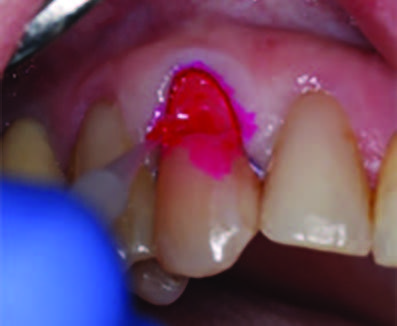

Figure 3. Application of caries indicator dye to identify the remaining infected tissue beneath the dislodged composite.